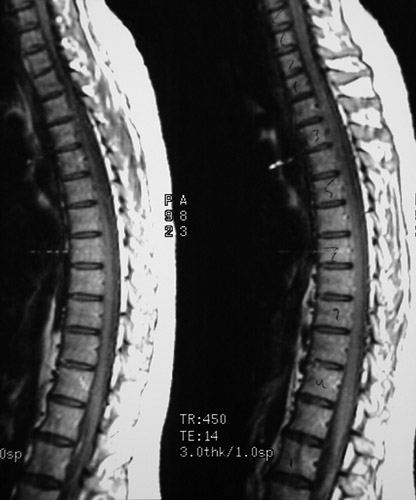

This is a normal sagittal MRI scan demonstrating the midline with the T1 vertebral body and T10 vertebral body.